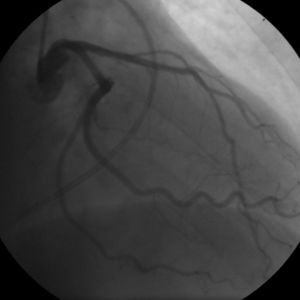

Coronary angiogram of a man

Coronary angiogram of a woman